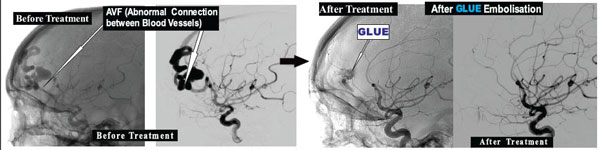

These are abnormal Connections between Arteries and Veins in Brain causing increase in pressure in Brain Veins causing Fits/ Epilepsy.

With Interventional Neuroradiological ,Without opening the Skull ; these Abnormal Connections between Arteries and Veins in Brain can be treated by technique of Glue Embolisation .

Example : 14 Yrs. girl presented with fits due to Brain PIAL AVF. After GLUE Embolisation of Brain AVM ,she didn’t have fits.